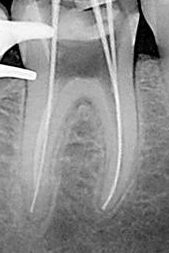

6-

Conductometría con RX:

consiste en determinar la longitud precisa entre el

CDC de cada

conducto y el borde incisal o la cara oclusal del diente en

tratamiento, considerando como longitud óptima 0,5 a 1mm. del ápice radiográfico

AR.

Pasos a

tener en cuenta

1.

Se

toma una radiografía inicial de diagnóstico

ortorradial, con el diente en el centro de la

placa, preferiblemente con técnica paralela. Se

mide la longitud de todo el diente desde el

borde incisal o cúspide oclusal hasta la porción

más apical del diente.

2.

resta 1 mm. a dicha longitud (distancia

existente entre ligamento periodontal y el CDC,

no observable en la radiografía). Conocer la

longitud promedio del diente es de gran ayuda

para determinar la longitud aproximada de

trabajo.

3.

Se desplaza el tope de silicona de una lima K

10 ( la elección del calibre de lima debe estar

relacionado con el espesor del conducto que

muestra la radiografía) y se aplica la longitud

radiográfica a la lima por medio de una regla.

4.

introduce la lima en el conducto correspondiente

hasta que el tope haga contacto con la

referencia anatómica elegida de la corona.

5.

toma una radiografía, una vez revelada se

verifica la ubicación del instrumento y se hacen

los ajustes necesarios, se considera que debe

estar ubicada a 0,5 – 1 mm del ápice

radiográfico.

6.

retira la lima del conducto y nuevamente se mide

la distancia entre el tope de goma y la punta

del instrumento, esta es la longitud de

trabajo definitiva. Se debe anotar en la

historia clínica las medidas de cada conducto y

el punto de referencia tomado para cada

conducto.